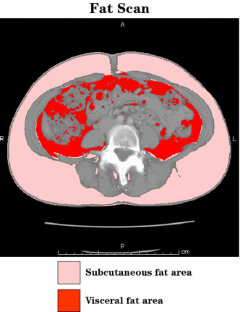

Between April 2002 and December 2007, 152 patients with preoperatively diagnosed early gastric cancer who underwent laparoscopy-assisted distal gastrectomy (LADG) were enrolled. Visceral (VFA) and subcutaneous fat areas (SFA) were assessed by Fat Scan software. The predictive factors for surgical complications of LADG were evaluated by univariate and logistic regression analyses.

Of 152 patients, conversion to open surgery due to uncontrollable bleeding was observed in nine male patients, and postoperative complications were detected in seven male and one female patient (four anastomotic leakage, two intraabdominal abscess, one pancreatic fistula, and one lymphorrhea). High body mass index (BMI) and high VFA independently predicted conversion to open surgery and postoperative complications. VFA was significantly higher, operation time was longer, blood loss was greater, and SFA was lower in male than in female patients, whereas no significant difference was observed in BMI between male and female patients.

High BMI and high VFA can predict technical difficulties during laparoscopic gastric surgery and postoperative complications. Particularly, LADG should be performed cautiously to prevent surgical complications for male patients with high VFA. Predictive impact of VFA should be further determined in a larger set of patients.